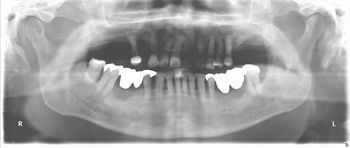

下顎fullインプラント

下顎のフルインプラントです。6本のインプラント(4本では不安です)を埋入して上部構造はスクリュウで固定してます。下の総義歯はみなさんどうしても浮き上がってきて食べにくいです。インプラントを埋入して即時負荷をかけるのはどうかと思いますが、骨と結合した後ならかなり頑丈な上部構造ができて、硬いものでも噛みやすくなります。

●● 様 男性 70代

治療の期間・回数:6か月、10回

治療の価格:150万円/下顎

治療のリスクや副作用:手術後に、痛みや腫れ、出血、合併症などを引き起こす可能性があります。噛む感覚がご自身の歯と異なる場合があります見た目がご自身の歯と異なる場合があります。手術後にメインテナンスを継続しないと抜け落ちる可能性があります。